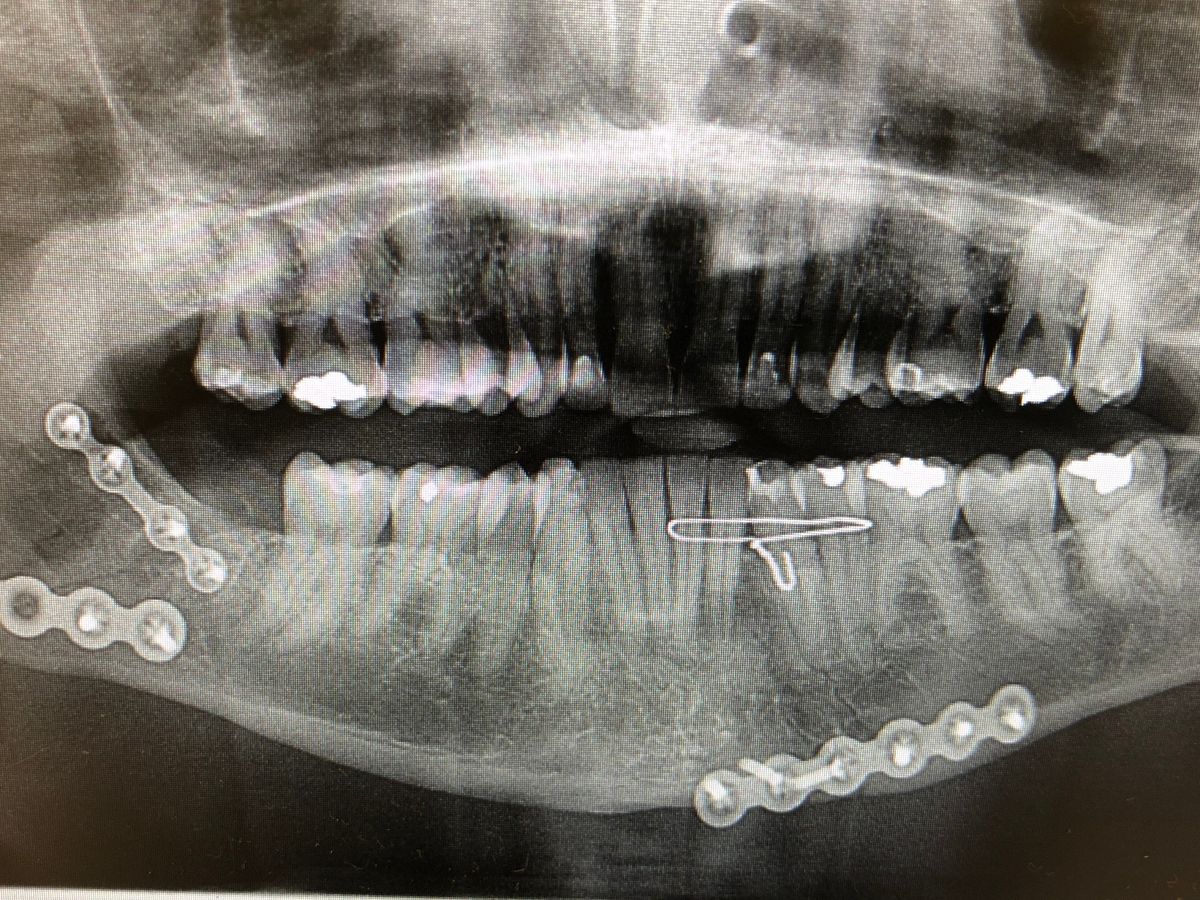

Late on November 23, 2020 when getting off the train he was attacked by 3 assailants and taken to Cook County Hospital in critical condition. His lower jaw was separated in 2 places causing extensive damage to his teeth and destroying the permanent retainer on his lower teeth. Also his nose was broken, major damage to his right eye socket, multiple cuts requiring stitches, and was concussed.

Three days later he had Oral Surgery to insert plates and screws to reconnect the lower jaw, remove a wisdom tooth and the permanent retainer. A second surgery the same day to repair his broken nose and stitch up the multiple cuts on his face from the attack. Surgeries were 5 hours combined with 4 more hours of recovery. After release he was given some vocal and other exercises to help prevent scarring and permanent limitation of his jaw. He was also advised to get a care provider for the 5 days post surgery.

Steve is now facing multiple root canals and crowns due to the separation in his jaw. Loss of the permanent retainer and wisdom tooth has also cause shifting of his lower teeth.